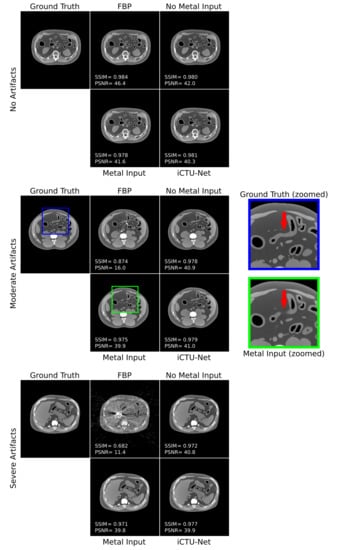

3. Results

3.3. Comparison Study